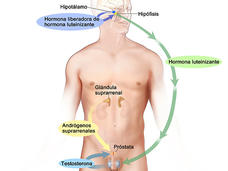

Terapia de combinación mejora la supervivencia de algunos hombres con cáncer recurrente de próstata

Resultados a largo plazo de un estudio clínico patrocinado por el NCI sugieren que la adición de terapia de privación de andrógenos a la radioterapia puede mejorar la supervivencia de algunos hombres con cáncer recurrente de próstata.